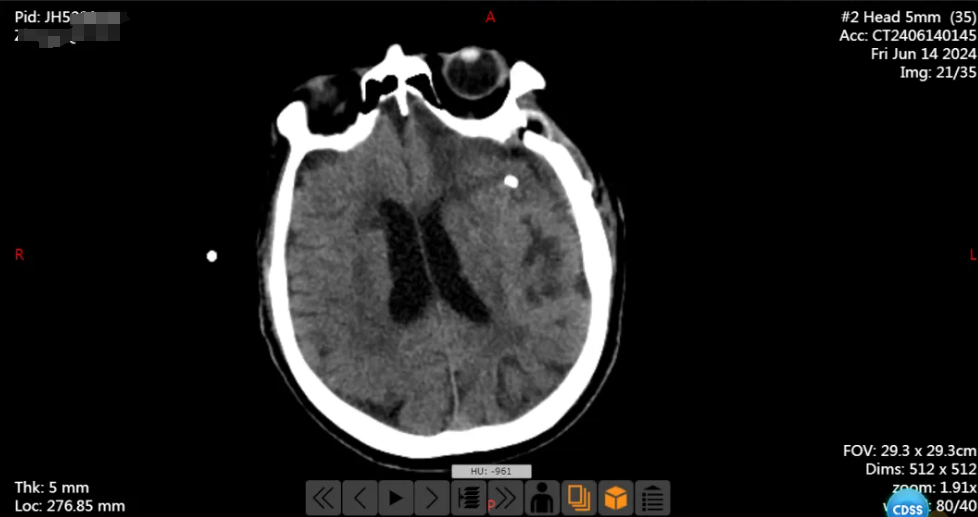

患者章爷爷(化姓),73 岁,安徽来安人,5 月 29 日晚上,因"被发现意识不清 2 小时"被送入外院就诊。接诊医生检查后发现他神志浅昏迷、无意识睁眼、不能言语、四肢肌力检查不配合等症状,做了头颅 CT 发现蛛网膜下腔出血。

手术很顺利,术后患者安返病房,复查头颅 CT 提示左侧大脑中动脉瘤夹闭完全,载瘤动脉通畅,继续予以对症支持治疗。